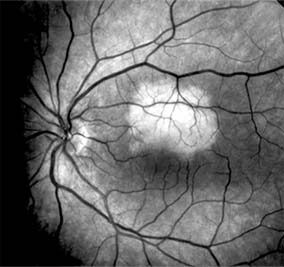

Central serous chorioretinopathy is characterized by serous detachment of the sensory retina as a consequence of focal leakage of fluid from the choriocapillaris through a defect in the retinal pigment epithelium (Figures 10-2 and 10-3). This disease typically affects young to middle-aged men and may be related to life stress events. Most patients present with the sudden onset of blurred vision, micropsia, metamorphopsia, and central scotoma. Visual acuity is often only moderately decreased and may be improved to near-normal with a small hyperopic correction.

Figure 10-2

Figure 10-2: Central serous chorioretinopathy with sensory retinal detachment (arrows) extending into the fovea.

Figure 10-3

Figure 10-3: Fluorescein angiogram of central serous chorioretinopathy shows active disease with both a retinal pigment epithelial detachment (small arrows) and a sensory retinal detachment (large arrows). Two foci of inactive disease (open arrows) are also present.